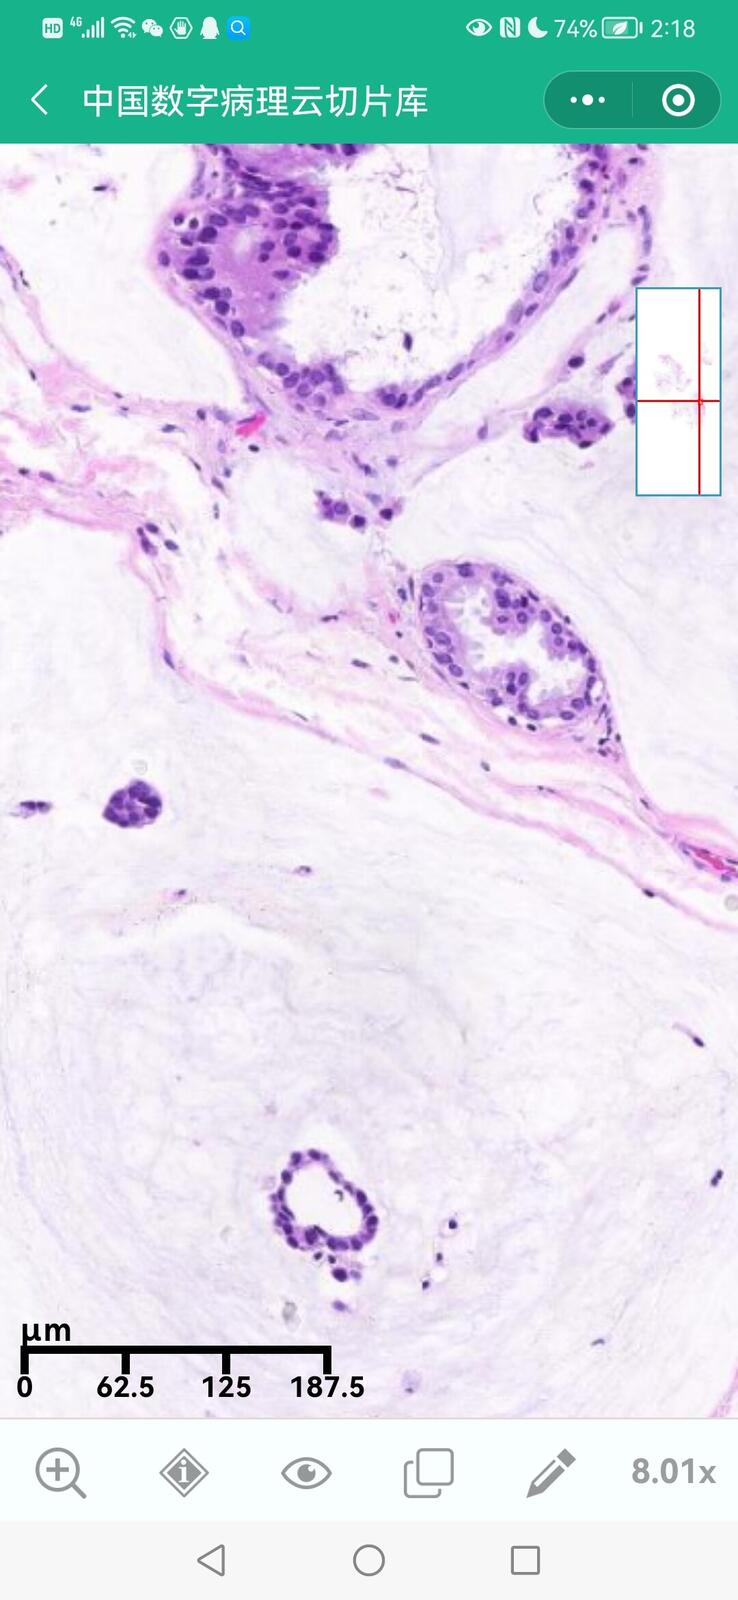

乳腺黏液性囊腺瘤伴导管内癌